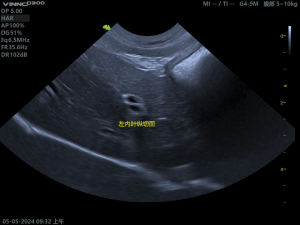

(2)胆囊粘液囊肿影像

胆囊内呈现“猕猴桃征”或“星芒状”的回声。胆囊壁增厚、胆泥淤积、可评估胆囊是否破裂。